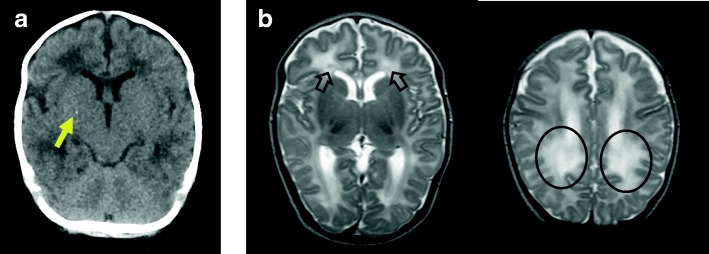

Intracranial calcification was observed on head computed tomography (CT) (Fig. 1,a arrow). Furthermore, T2-weighted brain magnetic resonance imaging (MRI) at 1.5 months of age (Fig. 1b) showed diffuse, abnormal, high-signal areas of white matter in the parietal and occipital lobes (round circles) as well as bilateral periventricular cysts (arrows) around the anterior horn of the lateral ventricle. There was no evidence of ventricular enlargement, polymicrogyria, or microcephaly. Chorioretinitis was ruled out by pediatric ophthalmologic examination.

Fig. 1.

CT and MRI findings. a Head CT scan at 1.5 months of age. The arrow indicates intracranial calcification. b Axial T2-weighted brain MRI at 1.5 months of age showing diffuse abnormalities of the white matter in the parietal, occipital, and frontal lobes (circle) as well as periventricular cysts (arrows) around the posterior horn of the bilateral lateral ventricles. No polymicrogyria, lissencephaly, or ventriculomegaly is observed